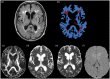

White matter hyperintensities accumulate with age and occur in patients with stroke, but their pathogenesis is poorly understood. We measured multiple magnetic resonance imaging biomarkers of tissue integrity in normal-appearing white matter and white matter hyperintensities in patients with mild stroke, to improve understanding of white matter hyperintensities origins. We classified white matter into white matter hyperintensities and normal-appearing white matter and measured fractional anisotropy, mean diffusivity, water content (T1-relaxation time) and blood-brain barrier leakage (signal enhancement slope from dynamic contrast-enhanced magnetic resonance imaging). We studied the effects of age, white matter hyperintensities burden (Fazekas score) and vascular risk factors on each biomarker, in normal-appearing white matter and white matter hyperintensities, and performed receiver-operator characteristic curve analysis. Amongst 204 patients (34.3-90.9 years), all biomarkers differed between normal-appearing white matter and white matter hyperintensities ( P < 0.001). In normal-appearing white matter and white matter hyperintensities, mean diffusivity and T1 increased with age ( P < 0.001), all biomarkers varied with white matter hyperintensities burden ( P < 0.001; P = 0.02 signal enhancement slope), but only signal enhancement slope increased with hypertension ( P = 0.028). Fractional anisotropy showed complex age-white matter hyperintensities-tissue interactions; enhancement slope showed white matter hyperintensities-tissue interactions. Mean diffusivity distinguished white matter hyperintensities from normal-appearing white matter best at all ages. Blood-brain barrier leakage increases with hypertension and white matter hyperintensities burden at all ages in normal-appearing white matter and white matter hyperintensities, whereas water mobility and content increase as tissue damage accrues, suggesting that blood-brain barrier leakage mediates small vessel disease-related brain damage.